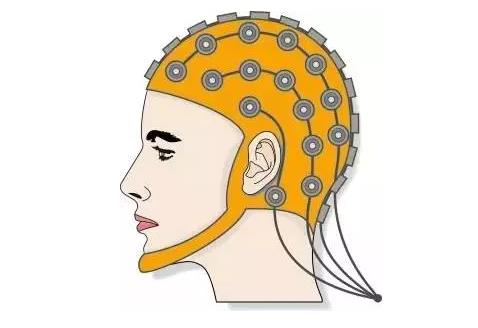

EEG(腦電圖)

規模: 高

解析度:空間上非常低,時間上中高

侵入性: 非侵入性

近一個世紀以來,EEG(腦電圖)把電極陣列罩在你頭上。你知道,就是這樣:33

EEG 對于一個2050年的人來說,絕對是一個非常原始的技術,但現在,它是可以BMI中完全無創的唯一工具。腦電圖記錄大腦不同區域的電活動,顯示出如下結果:34 34

腦電圖可以揭示有關醫療問題的信息,如癲癇癥等。與fMRI不同,EEG從腦中獲取電信號具有相當好的時間解析度,——盡管頭骨大大地模糊了時間精度(骨骼是壞導體)。

主要缺點是空間解析度。每個電極僅記錄來自數百萬或數十億神經元電荷的廣泛平均矢量和。

想象一下,大腦是一個棒球場,它的神經元是人群。我們想要的信息,不是電子活動,而是聲帶活動。在這種情況下,腦電圖就像一組麥克風,放在體育場外面,靠在體育館的外墻上。你可以聽到人群的歡呼聲,也許可以預測他們正在歡呼的事情。你可以聽到指示牌變化的跡象。你可能會發現一些異常。但也就這樣了。

EEG(腦電圖)

規模: 高

解析度:空間上非常低,時間上中高

侵入性: 非侵入性

近一個世紀以來,EEG(腦電圖)把電極陣列罩在你頭上。你知道,就是這樣:33

EEG 對于一個2050年的人來說,絕對是一個非常原始的技術,但現在,它是可以BMI中完全無創的唯一工具。腦電圖記錄大腦不同區域的電活動,顯示出如下結果:34 34

腦電圖可以揭示有關醫療問題的信息,如癲癇癥等。與fMRI不同,EEG從腦中獲取電信號具有相當好的時間解析度,——盡管頭骨大大地模糊了時間精度(骨骼是壞導體)。

主要缺點是空間解析度。每個電極僅記錄來自數百萬或數十億神經元電荷的廣泛平均矢量和。

想象一下,大腦是一個棒球場,它的神經元是人群。我們想要的信息,不是電子活動,而是聲帶活動。在這種情況下,腦電圖就像一組麥克風,放在體育場外面,靠在體育館的外墻上。你可以聽到人群的歡呼聲,也許可以預測他們正在歡呼的事情。你可以聽到指示牌變化的跡象。你可能會發現一些異常。但也就這樣了。